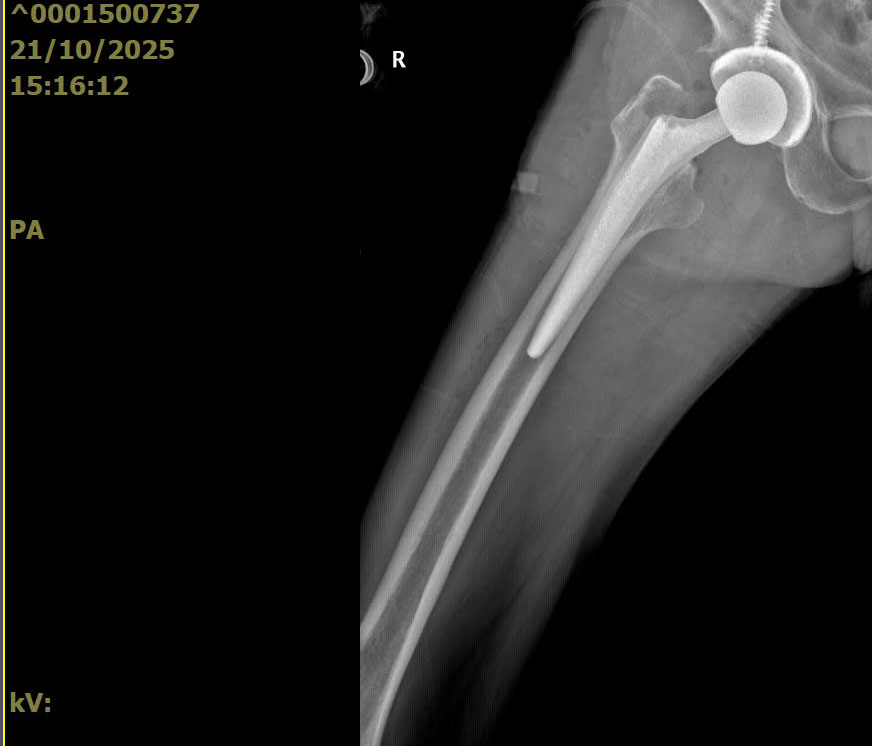

Trong tuần vừa qua, các bác sĩ Trung tâm Y tế Đông Triều đã tiếp nhận và phẫu thuật thay khớp háng cho 04 bệnh nhân cao tuổi, trong đó có 02 bệnh nhân do nguyên nhân gãy cổ xương đùi và 02 bệnh nhân do hoại tử chỏm xương đùi. Trước thực trạng bệnh lý vùng khớp háng cần phải phẫu thuật ngày càng gia tăng, Bác sĩ CKII Hà Duy Nam – Phó Giám đốc Trung tâm Y tế TP Đông Triều khuyến cáo người dân cần lưu ý bốn nguyên nhân phổ biến gây tổn thương khớp háng ở người cao tuổi: